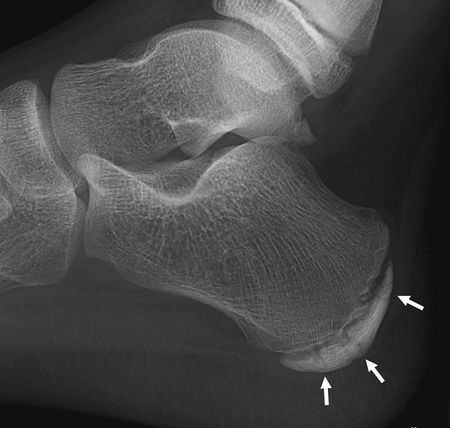

休息時候痛楚點明顯得到緩減臨床上,醫護人員會檢查傷患的位置並作出一些特定的測試包括:觸診、關節活動幅度及肌肉柔軟度、擠壓測試(Squeeze Test)、足尖站立及步姿檢查等等從而作出準確的臨床診斷。X-光檢查可排除其他足跟痛的成因。治療一般以物理治療、藥物及伸展運動為主,包括:

X光下所見的跟骨生長板 小腿伸展運動